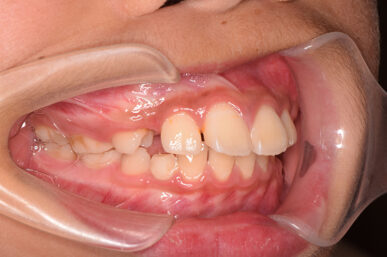

• Before

治療開始が遅くてこのままでは犬歯の生えるスペースが不足していて八重歯になるところでしたが、アライナー矯正で素早く歯を動かして犬歯が生えてくるスペースを作ることで八重歯にならずに済みました。

八重歯のケースは永久歯の抜歯が必要になることもありますが、避けることができました。